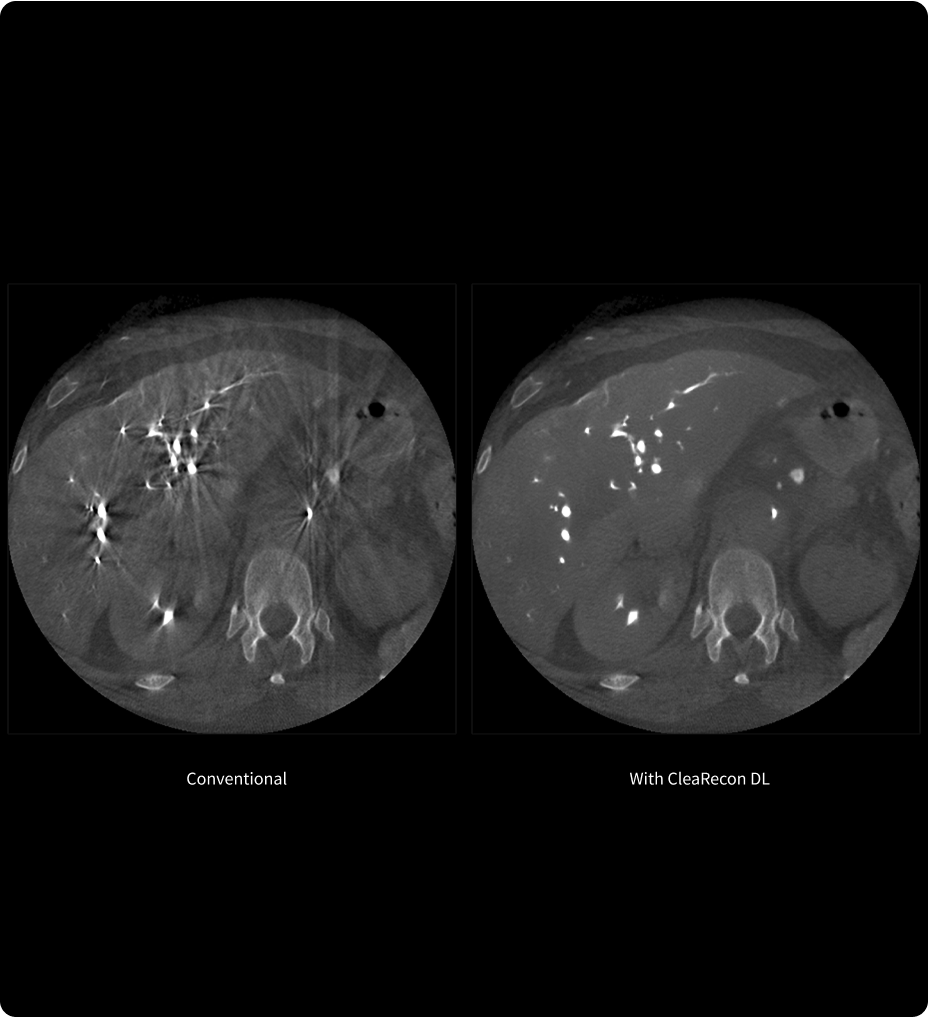

TrueFidelity DL

Deep learning for a deeper understanding

TrueFidelity™ DL is our state-of-the-art image reconstruction technology that uses a DNN to generate high-definition, low-noise CT images. It produces images with exceptional sharpness, low-contrast image quality performance and your preferred noise texture, at the same dose.¹